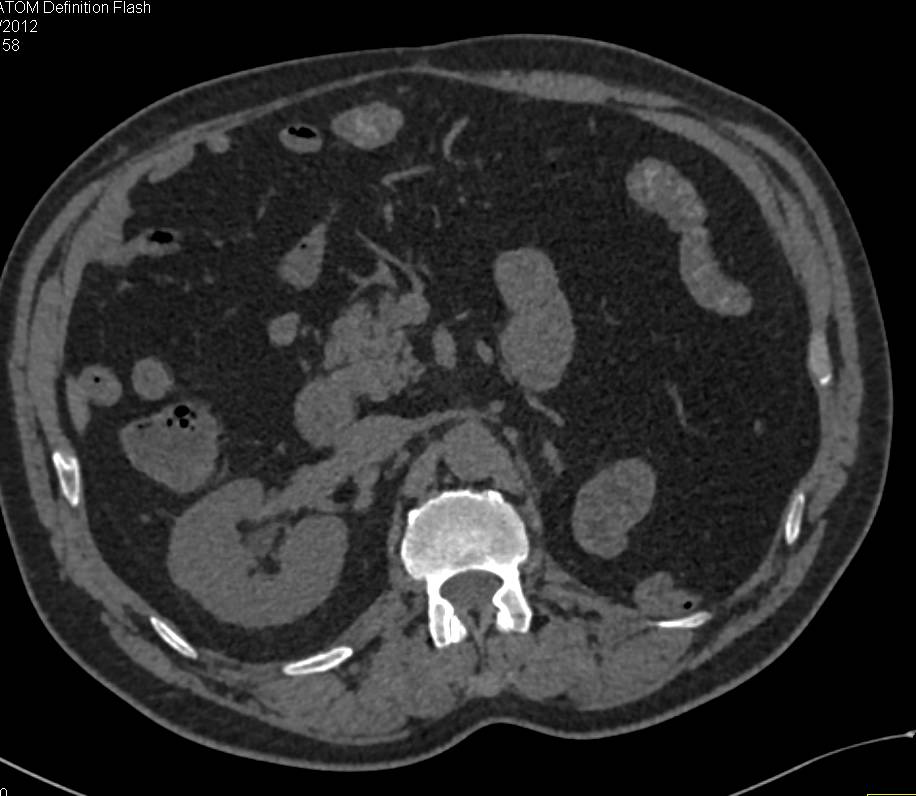

Incidental 8 mm Right Renal Cell Carcinoma